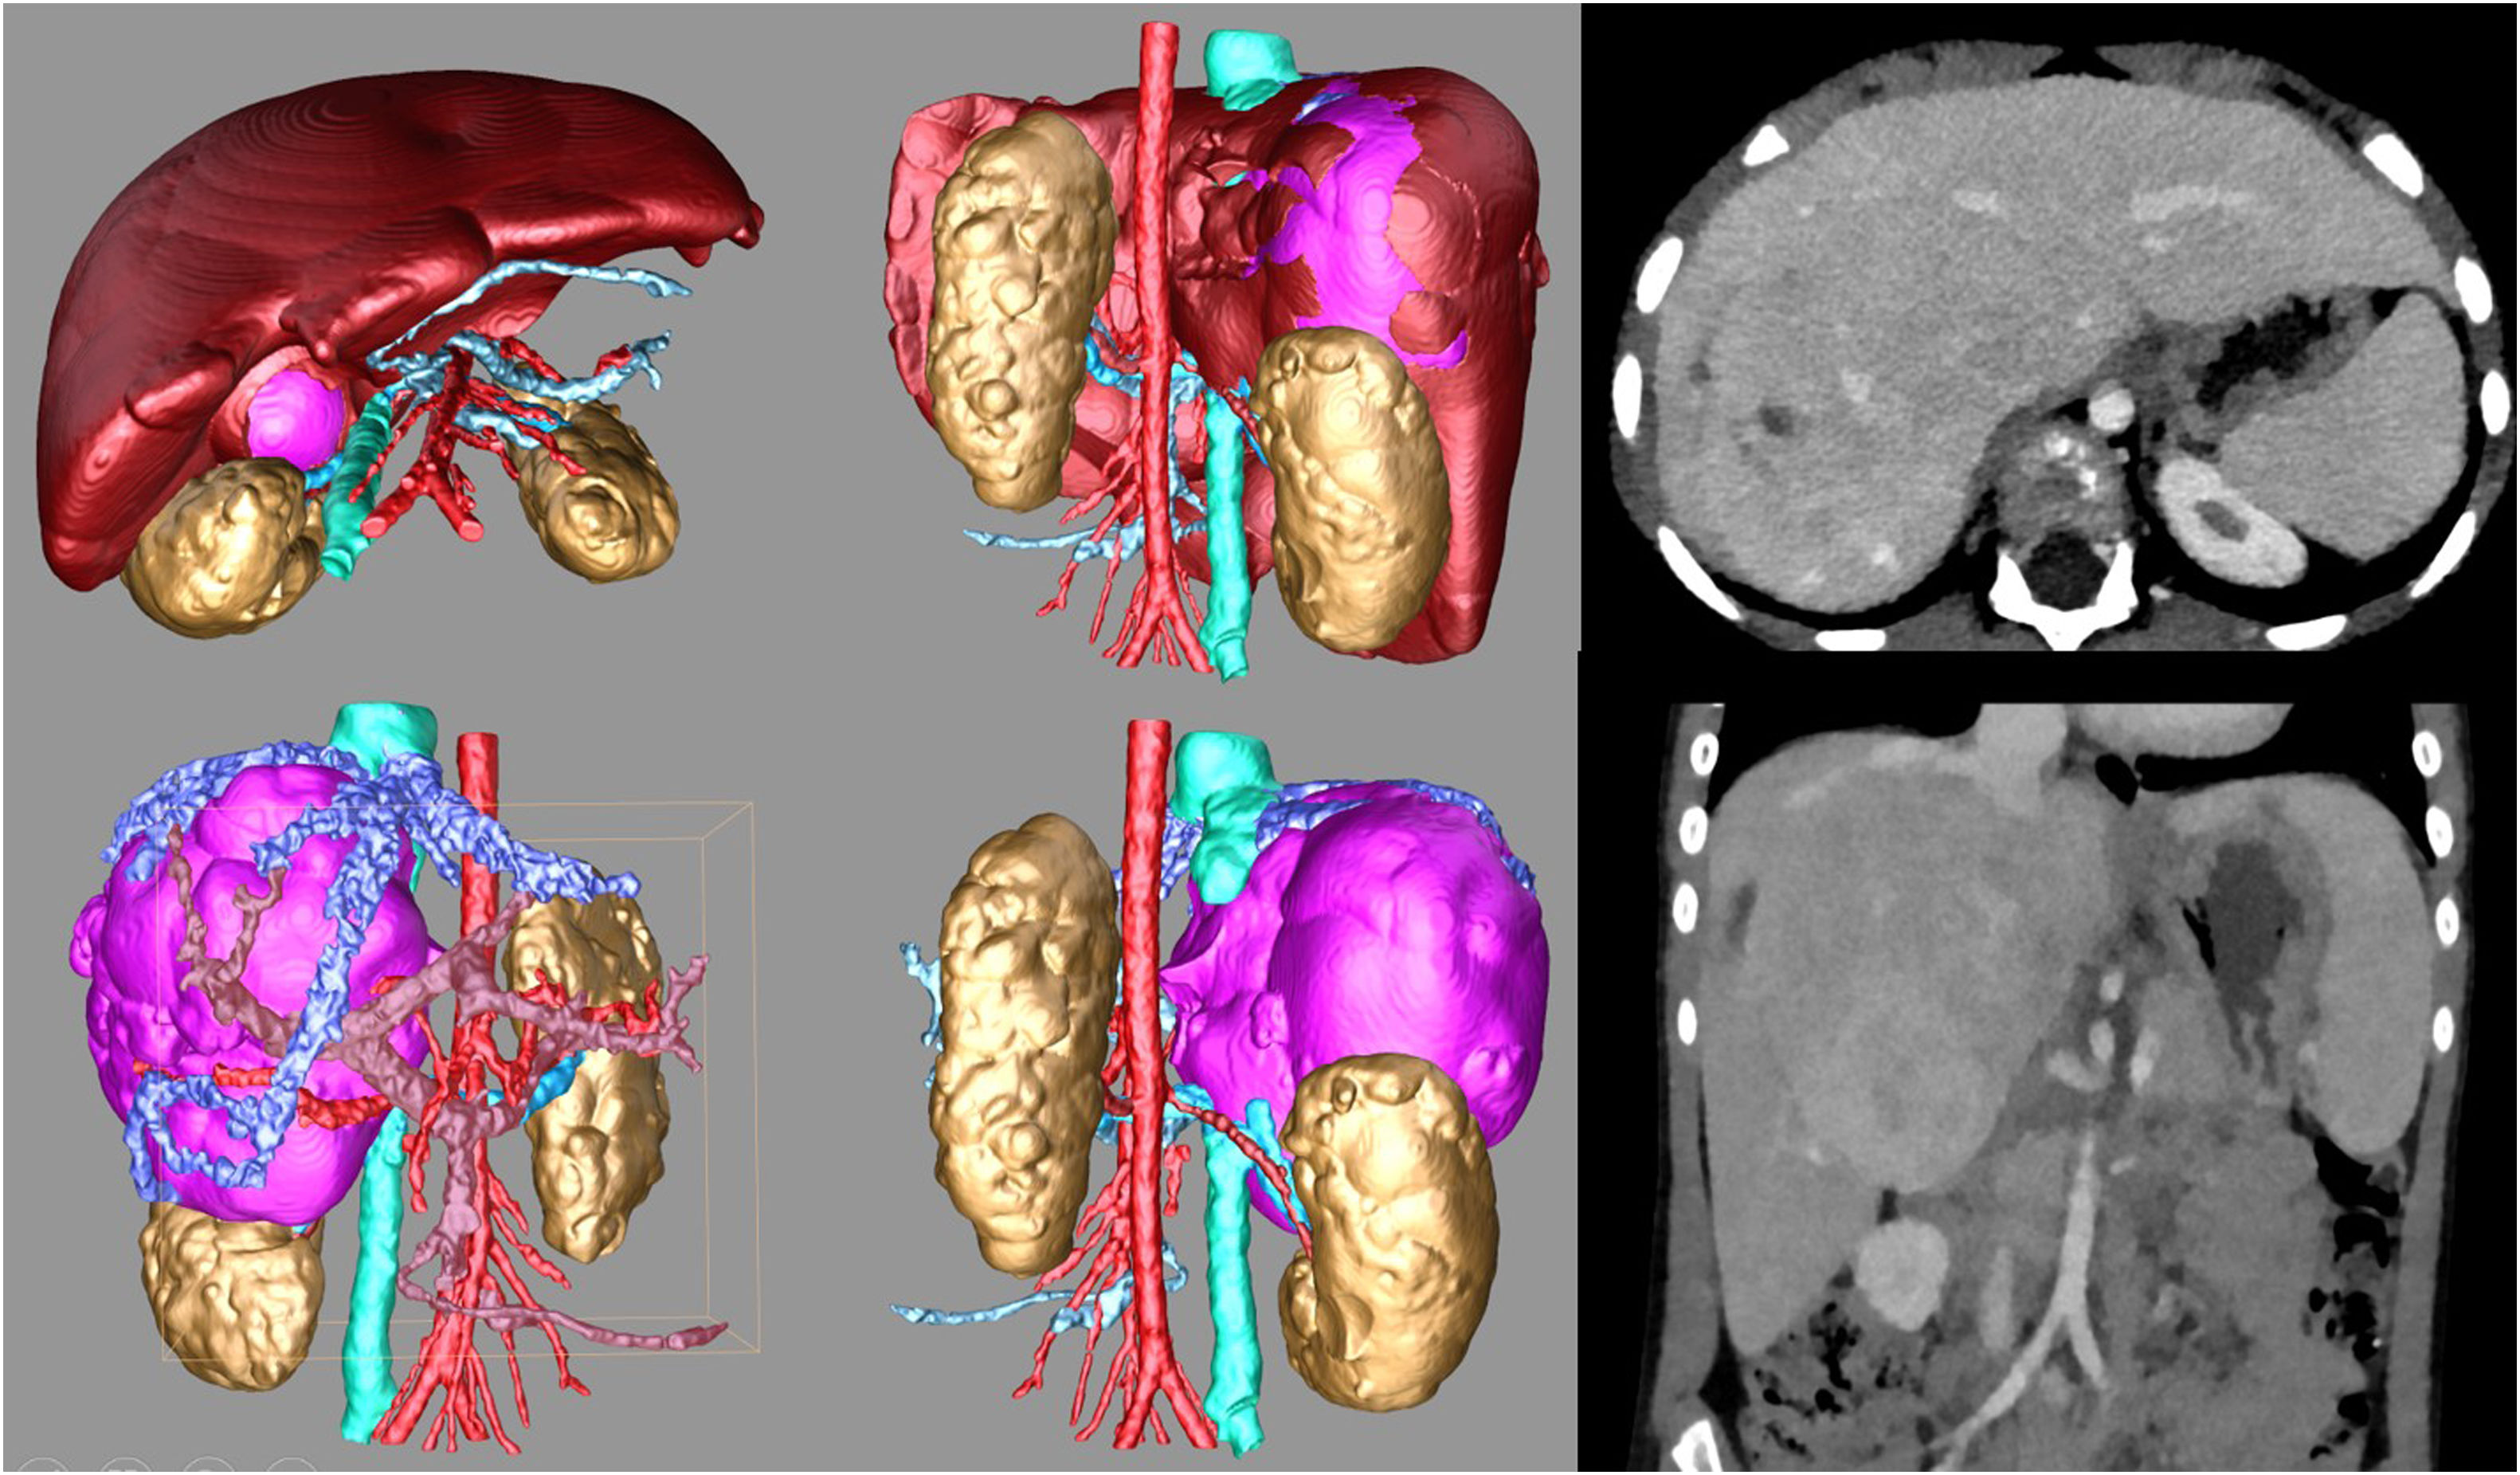

Avances en tomografía computarizada (TC)Las tecnologías modernas de TC incluyen sistemas de doble energía y de conteo de fotones que mejoran la calidad de la imagen y reducen la dosis de irradiación. Los escáneres de TC de doble energía (dual-energy CT) pueden generar imágenes virtuales sin contraste que permiten visualizar cálculos renales en estudios con contraste, así como mapas de yodo que pueden ser útiles para visualizar la perfusión pulmonar en casos de embolia pulmonar. Los escáneres de TC con conteo de fotones (photon-counting CT [PCCT]) generan imágenes de mejor calidad con dosis de radiación y volúmenes de contraste menores. Se estima que la PCCT podría reducir las dosis de radiación en aproximadamente un 30-60%, dependiendo del protocolo de imagen y la cuestión clínica2. Estos avances permiten ya obtener mapas de cuantificación de captación de yodo, mejorando la diferenciación tisular, una mejor segmentación y reconstrucción tridimensional de las lesiones tumorales, con mejoría de la reconstrucción tridimensional e impresión 3D, facilitando la planificación de cirugías complejas y la integración de la imagen con la robótica quirúrgica, permitiendo así avances en la cirugía guiada por imagen (figura 1).